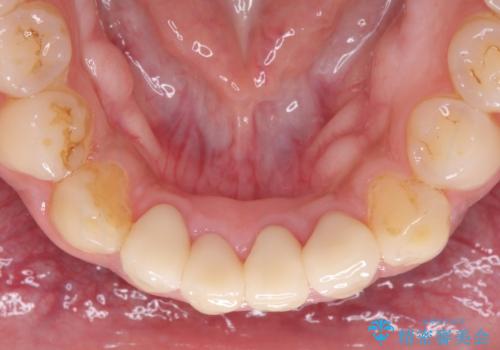

根管治療により腫れと痛みが引き、叢生の認められた歯列は補綴治療により改善され、清掃性が増しました。

歯が失活してしまうほどの咬合力であるため、就寝時にはマウスピースを装着していただくようお願いしました